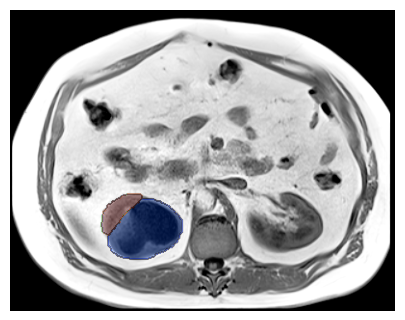

Purpose: To introduce a deep learning model capable of multi-organ segmentation in MRI scans, offering a solution to the current limitations in MRI analysis due to challenges in resolution, standardized intensity values, and variability in sequences. Materials and Methods: he model was trained on 1,200 manually annotated MRI scans from the UK Biobank, 221 in-house MRI scans and 1228 CT scans, leveraging cross-modality transfer learning from CT segmentation models. A human-in-the-loop annotation workflow was employed to efficiently create high-quality segmentations. The model's performance was evaluated on NAKO and the AMOS22 dataset containing 600 and 60 MRI examinations. Dice Similarity Coefficient (DSC) and Hausdorff Distance (HD) was used to assess segmentation accuracy. The model will be open sourced. Results: The model showcased high accuracy in segmenting well-defined organs, achieving Dice Similarity Coefficient (DSC) scores of 0.97 for the right and left lungs, and 0.95 for the heart. It also demonstrated robustness in organs like the liver (DSC: 0.96) and kidneys (DSC: 0.95 left, 0.95 right), which present more variability. However, segmentation of smaller and complex structures such as the portal and splenic veins (DSC: 0.54) and adrenal glands (DSC: 0.65 left, 0.61 right) revealed the need for further model optimization. Conclusion: The proposed model is a robust, tool for accurate segmentation of 40 anatomical structures in MRI and CT images. By leveraging cross-modality learning and interactive annotation, the model achieves strong performance and generalizability across diverse datasets, making it a valuable resource for researchers and clinicians. It is open source and can be downloaded from https://github.com/hhaentze/MRSegmentator.